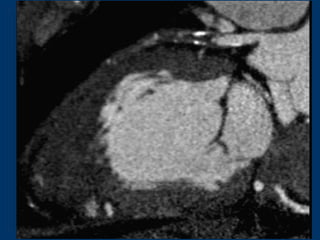

LCX Anomaly and Stenosis

Perfusion Defect